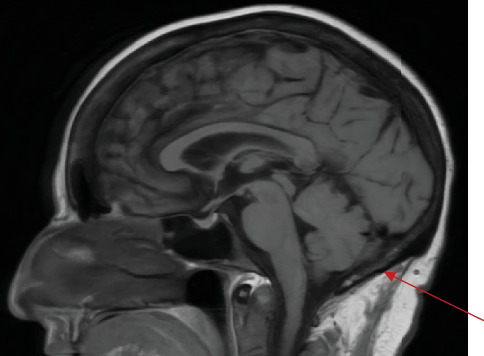

乳腺癌可扩散到大脑和骨骼,通常分别表现为实质和成骨细胞病变。我们提出一个独特的情况下,59岁的妇女接受治疗浸润性小叶乳腺癌谁提出恶心,呕吐,头痛,和全身无力。她的临床表现和随后的评估导致发现轻脑膜癌和髓鞘性贫血同时出现在她的初始转移。她每周接受紫杉醇和鞘内甲氨蝶呤治疗,脑脊液有明显反应。她继续在肿瘤诊所跟进。

Breast cancer can spread to the brain and bone, usually presenting as parenchymal and osteoblastic lesions, respectively. We present a unique case of a 59-year-old woman undergoing treatment for invasive lobular breast cancer who presented with nausea, vomiting, headache, and generalized weakness. Her clinical presentation and subsequent evaluation led to a discovery of leptomeningeal carcinomatosis and myelophthisic anemia presenting simultaneously as her initial metastases. She was treated with weekly paclitaxel and intrathecal methotrexate, with noted cerebrospinal fluid response. She continues to follow up with the oncology clinic.